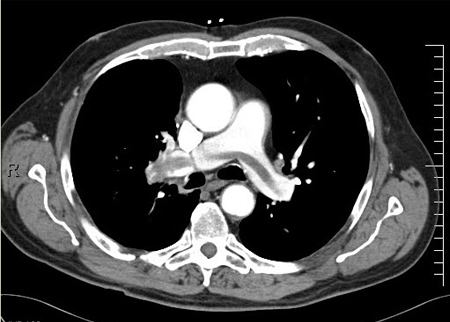

- TC do tórax com contraste:

falso lúmen ou "flap" na aorta ascendente ou descendente

Dissecção da aorta

História

sensação aguda de rasgo subesternal, com irradiação para a região interescapular no dorso; a dor pode migrar com a propagação da dissecção; AVC, infarto agudo do miocárdio devido a obstrução dos ramos aórticos; dispneia devida a regurgitação aórtica aguda; hipotensão devida a tamponamento cardíaco; história de hipertensão, síndrome de Marfan, síndrome de Ehlers-Danlos ou sífilis

Exame físico

pulsos ou pressões arteriais desiguais em ambos os braços; novo sopro diastólico devido à regurgitação aórtica; bulhas cardíacas hipofonéticas se a dissecção for complicada por tamponamento cardíaco; novos achados neurológicos focais decorrentes de envolvimento das artérias carótidas ou vertebrais

Primeira investigação

- radiografia torácica:

mediastino alargado